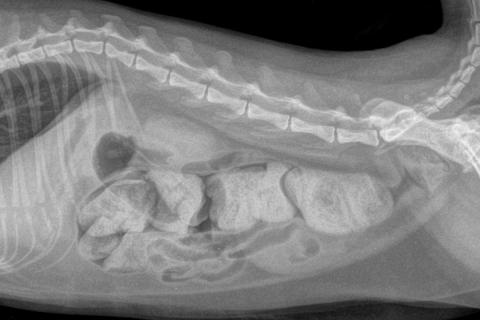

На снимке видно инородное тело, которое вызвало непроходимость кишечника у собаки.

Кишечная непроходимость на снимке.